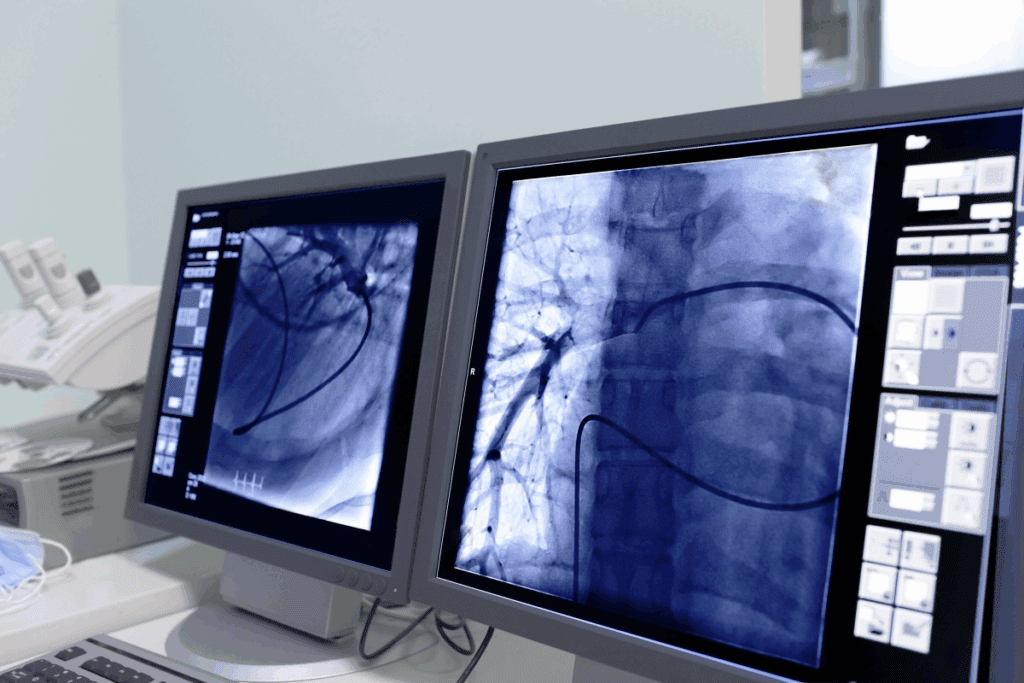

Advanced imaging systems have changed the game in interventional pain management. They offer precise guidance during procedures. This is key for the accuracy and safety of many techniques.

Fluoroscopy is a top choice in interventional pain management. It shows what’s happening in real-time. This helps place needles and instruments exactly right.

For things like epidural steroid injections and nerve blocks, fluoroscopy is a game-changer. It lets us guide the needle to the right spot. This cuts down on risks and boosts patient results.